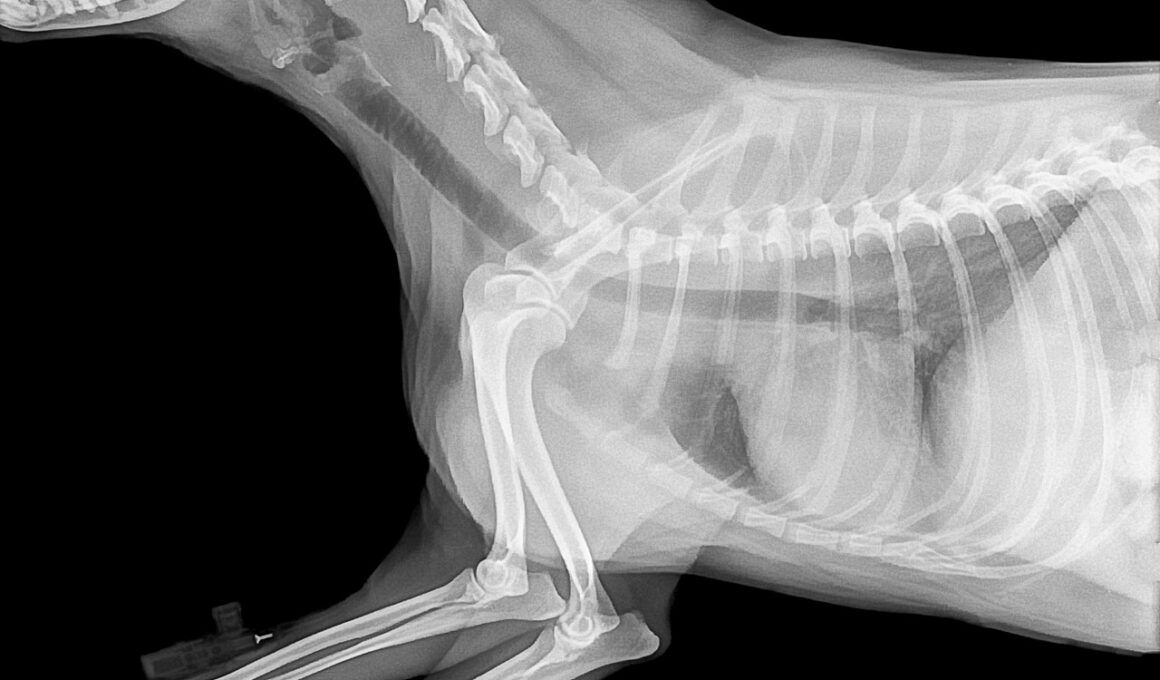

Common Bone Disorders in Dogs and How to Prevent Them

Bone disorders in dogs can significantly impact their quality of life, affecting mobility, behavior, and overall health. One of the most common issues is hip dysplasia, where the hip joint does not fit properly into the hip socket. This malformation can lead to arthritis and severe pain. Osteochondritis dissecans (OCD) is another disorder, often seen in large breeds, where cartilage becomes damaged, affecting joint function. Other examples include luxating patella and bone fractures. These conditions are particularly challenging as they can develop silently over time, making it crucial for dog owners to be vigilant. Regular vet check-ups become essential to catch these issues early on. Maintaining an appropriate weight, providing supportive nutrition, and engaging in moderate exercise are fundamental preventive measures. Dog breeds may have specific predispositions to certain bone disorders, making awareness important. Identifying early symptoms like limping, decreased activity, or reluctant movement should prompt immediate veterinary consultation. Thus, understanding these bone disorders is an essential step towards ensuring your dog’s long-term health and comfort. Through proper preventive care, you can help address and mitigate these common issues.